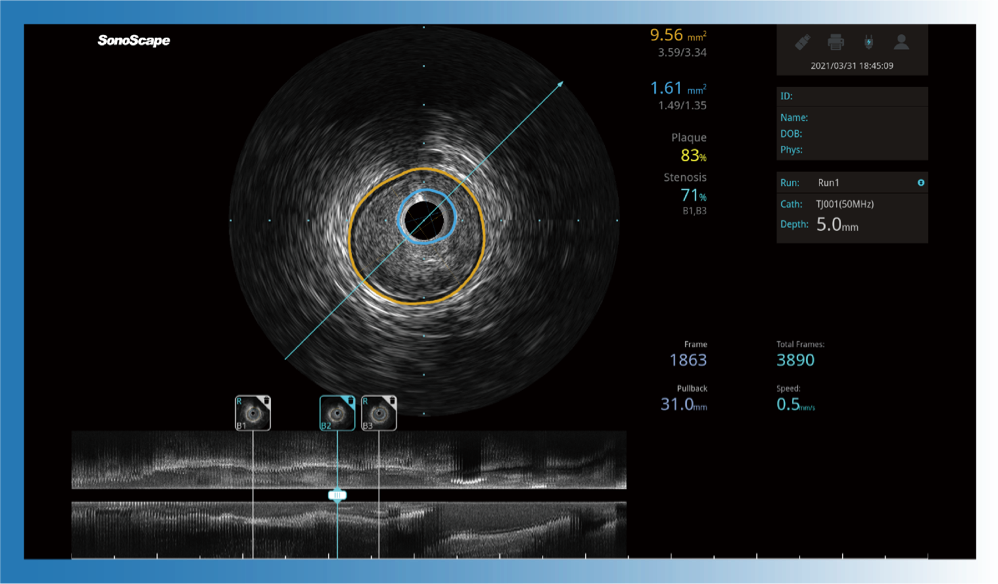

一键智能描迹,自动测量斑块负荷、面积狭窄率等指标,准确率高于90%